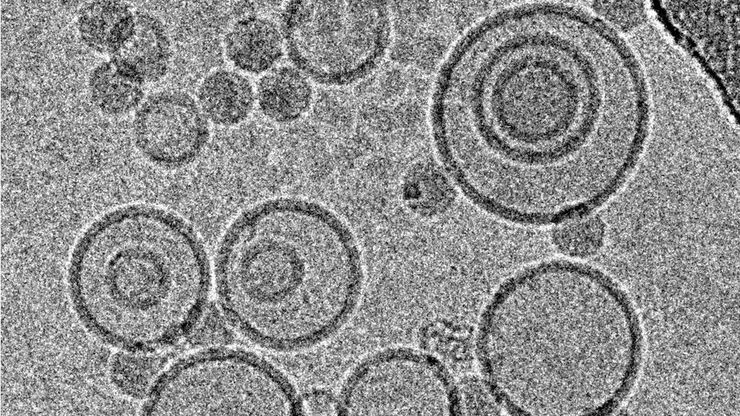

Cryo-electron micrographs of subviral particles of a common cold virus bound to liposomes, acquired under low dose conditions at 300 kV with a CCD-camera.

冷冻透射电子显微镜的投入式冷冻技术:应用

低温下观察完全含水、未染色样本的透射电子显微镜(cryo TEM)是结构生物学、细胞生物学、药理学和其他科学分支的通用工具。通过将标本放入冷冻剂中进行超快速冷冻(投入式冻结)是一种常用的方法,用于制备在透射电镜观察的各种标本。本文是对投入式冷冻的补充,介绍了在不同领域使用投入式冷冻标本的三种冷冻TEM应用。